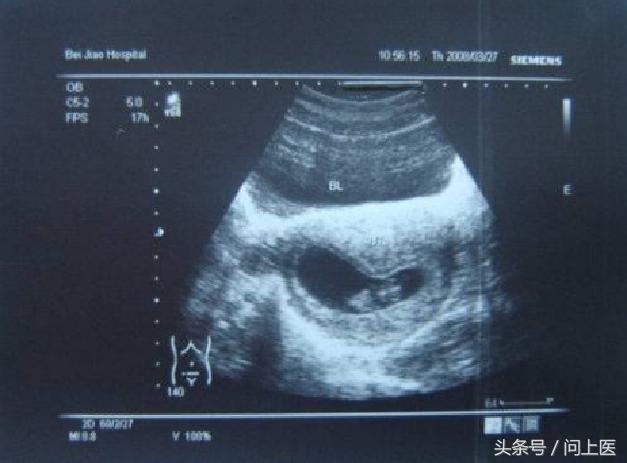

2.照B超或彩超

(1)如何做?

一般而言,在胎儿4个月之后可通过B超明确胎儿性别。

(2)科学原理

经过一定时间的发育,胎儿的外生殖器特征会逐渐显现。有医生指出,在B超图像上,男胎的生殖器大致是壶把儿状,女胎的则大致是花瓣状,可据此判断胎儿性别。

(3)准确性

胎儿外生殖器发育越完全,准确性越高。在怀孕11周时,B超的错误率可达40%,到了13周的时候,有经验的医生的判断正确率可接近100%。此外,其准确性受检测医师的经验所影响,总体而言B超判断的准确度可达85%~90%左右。

(4)有无危害?

B超是一种利用超声波检测的技术手段,目前无任何报告显示它对胎儿有不良影响,其在妇产科界使用非常普遍。